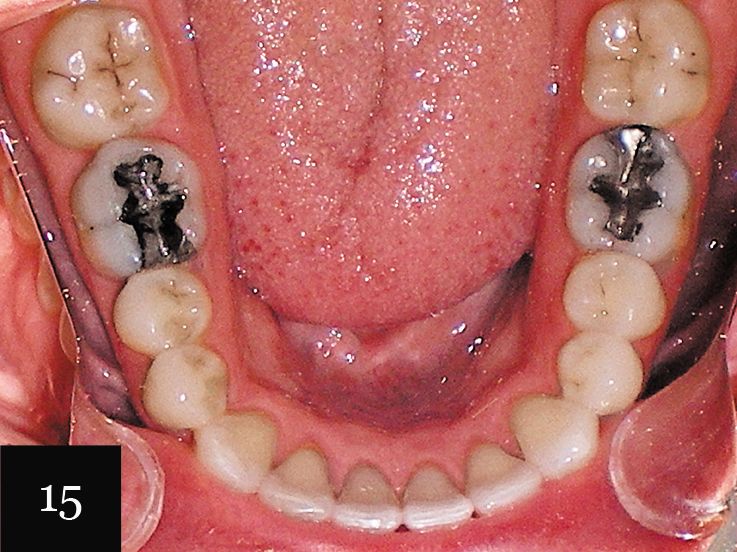

This case was performed on a patient in her late teens who presented with a very deep bite and severe crowding, as seen in Figs. 15-17.

The patient had consulted with multiple dentists who informed her that the lower lateral incisor would have to be extracted and that she was not a candidate for Invisalign. However, with an accurate impression we were indeed able to successfully treat this case with Invisalign, first using a series of 27 aligners, and then following up with an additional impression and eight more aligners for refinement (Figs. 18-20).